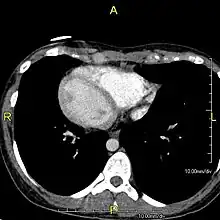

However, in some individuals with PCD, mutations thought to be in the gene coding for the key structural protein left-right dynein (lrd)[4] result in monocilia which do not rotate. There is therefore no flow generated in the node, Shh moves at random within it, and 50% of those affected develop situs inversus, which can occur with or without dextrocardia, where the laterality of the internal organs is the mirror-image of normal. Affected individuals therefore have Kartagener syndrome. This is not the case with some PCD-related genetic mutations: at least 6% of the PCD population have a condition called situs ambiguus or heterotaxy, where organ placement or development is neither typical (situs solitus) nor totally reversed (situs inversus totalis) but is a hybrid of the two.[6] Splenic abnormalities such as polysplenia, asplenia and complex congenital heart defects are more common in individuals with situs ambiguus and PCD, as they are in all individuals with situs ambiguus.[18]

When accompanied by the combination of situs inversus (reversal of the internal organs), chronic sinusitis, and bronchiectasis, it is known as Kartagener syndrome[3] (only 50% of primary ciliary dyskinesia cases include situs inversus).[11]